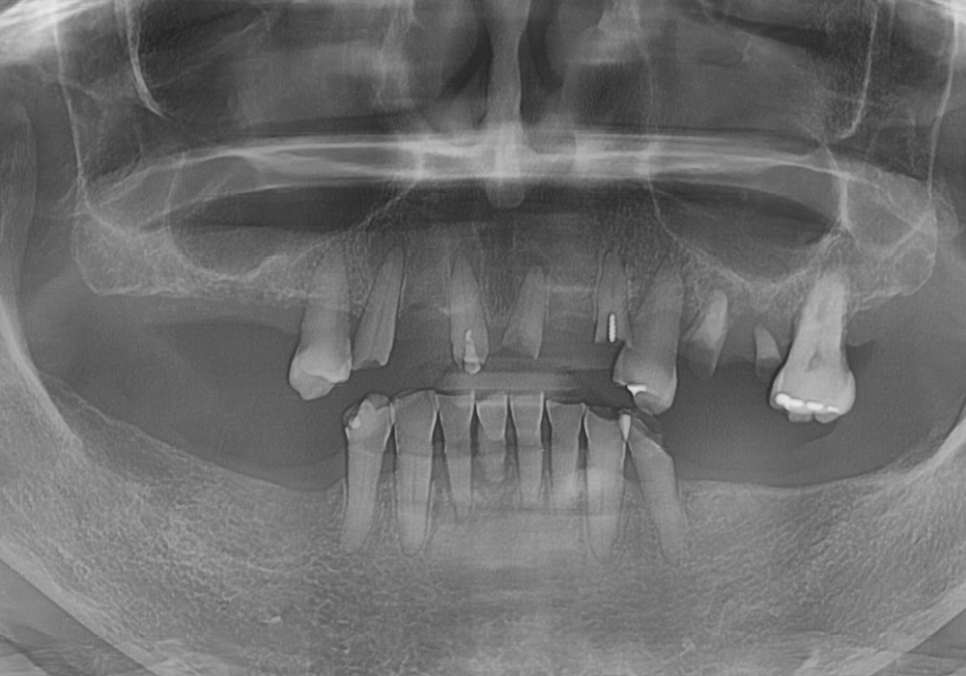

아래턱은 양쪽 어금니를

상실한 지 오래되셨고,

위턱은 대부분의 치아가

뿌리만 겨우 매달려 있었습니다.

230817

파노라마와 CT를 통해 살펴보니

뿌리 끝에 염증이 가득 잡혀 있었죠.

230902

가장 튼튼해서 살려 쓸 수 있는

위쪽 치아 2개(#14, 27)만 남기고

나머지는 안타깝게도 발치를 결정했습니다.

아래쪽 앞니들은 잇몸뼈가 많이 녹아 흔들리고 있어

총 4개의 치아를 발치하기로 했습니다.